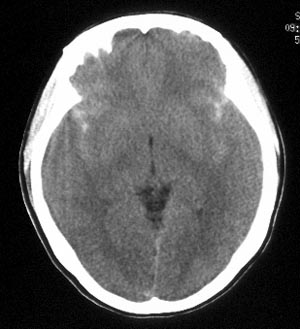

女性,36岁。头部外伤半小时,现觉头痛,有呕吐,无昏迷。

ct平扫:双侧脑沟、脑裂见密度增高,双侧大脑半球及颅后窝脑实质未见异常密度改变。

ct诊断:蛛网膜下腔出血。